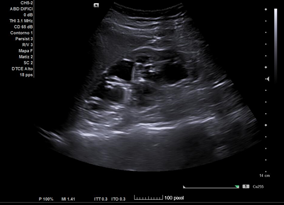

En ecografía clínica desde el centro de salud, se objetiva gran dilatación del sistema excretor del riñón derecho, con adelgazamiento de la cortical (hidronefrosis grado III-IV). No se aprecia litiasis u otra causa obstructiva a nivel renoureteral ni vesical. Riñón derecho conserva tamaño normal. Riñón izquierdo de tamaño y ecoestructura normales, sin dilatación piélica. Vejiga bien replecionada sin alteraciones en su pared.

Juicio Clínico: Riñón derecho con dilatación de su sistema excretor.

Concordancia con el hospital. Se realiza Urografía por Tomografía Computada que confirma hidronefrosis grado IV en riñón derecho; no se objetivan litiasis renoureterales; se aprecia arteria accesoria polar inferior de dicho riñón, la cual cruza la unión pieloureteral ipsilateral.